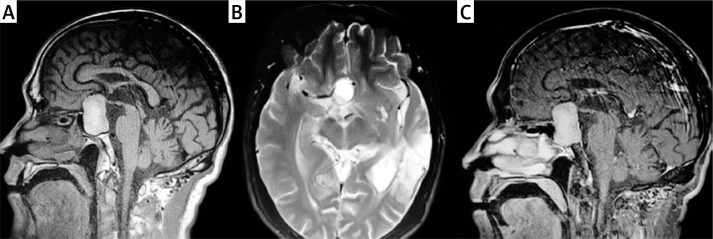

Effectiveness of endoscopic transnasal pituitary surgery versus antibiotic therapy in the management of pituitary abscess: a report of two cases.